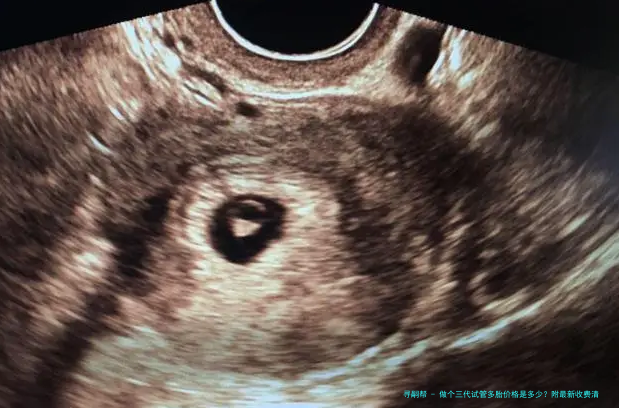

试管婴儿通过体外受精和胚胎移植的方式帮助不行自行受孕的夫妻完成生育心愿。这个技术慢慢形成为解决试管婴儿问题的有效手段。

三代试管婴儿是近年来发展起来的一项新技术,对比2代试管婴儿具有更高的成功率。它选用了新一代辅助生殖器械和先进的胚胎筛查技术,可以提高受孕率并减轻遗传病症风险。

三代试管多个胎儿指同一时间移植2个经由筛查后优异发育的胚胎,以增加成功率。